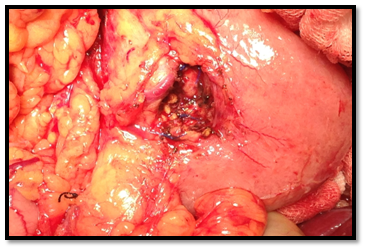

In September of 2014, she underwent a tumour enucleation, without complications (Figure 4). In the postoperative period the patient resolved symptoms and hypoglycaemia did not recur. The histopathological study confirmed a low-grade neuroendocrine tumour with high reactivity to a-chromogranin and synaptophysin (Figure 5A-D). Seven months post-surgery she didn’t present hyperglycaemia or diabetes mellitus.

• Figure 4 Surgery. Tumor enucleation.